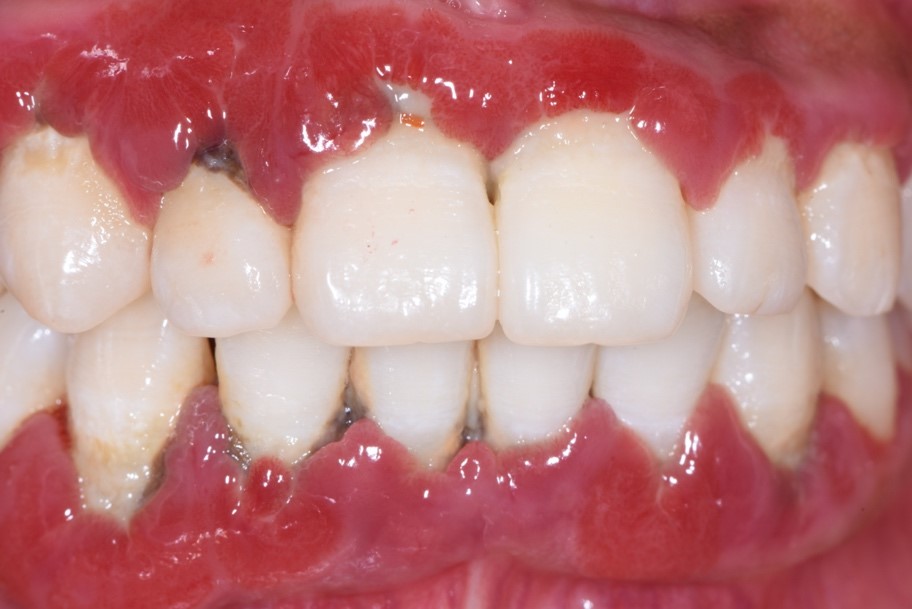

图2:长期口腔清洁不到位,牙菌斑、牙石堆积,刺激牙龈肿胀充血发炎

其中,导致牙龈出血最主要的原因是牙周病,包括牙龈炎或牙周炎。牙周病是人类最常见的疾病之一,它是一类感染炎症性疾病,由牙菌斑生物膜感染及人体免疫炎症反应失衡引发。牙周病是我国成年人失牙的主要原因,并且与糖尿病、心血管疾病等多种全身疾病密切相关。严重的牙周炎患者常面临多颗牙缺失、咀嚼功能障碍等问题,严重影响患者自身的营养、生活质量、言语及美观等。